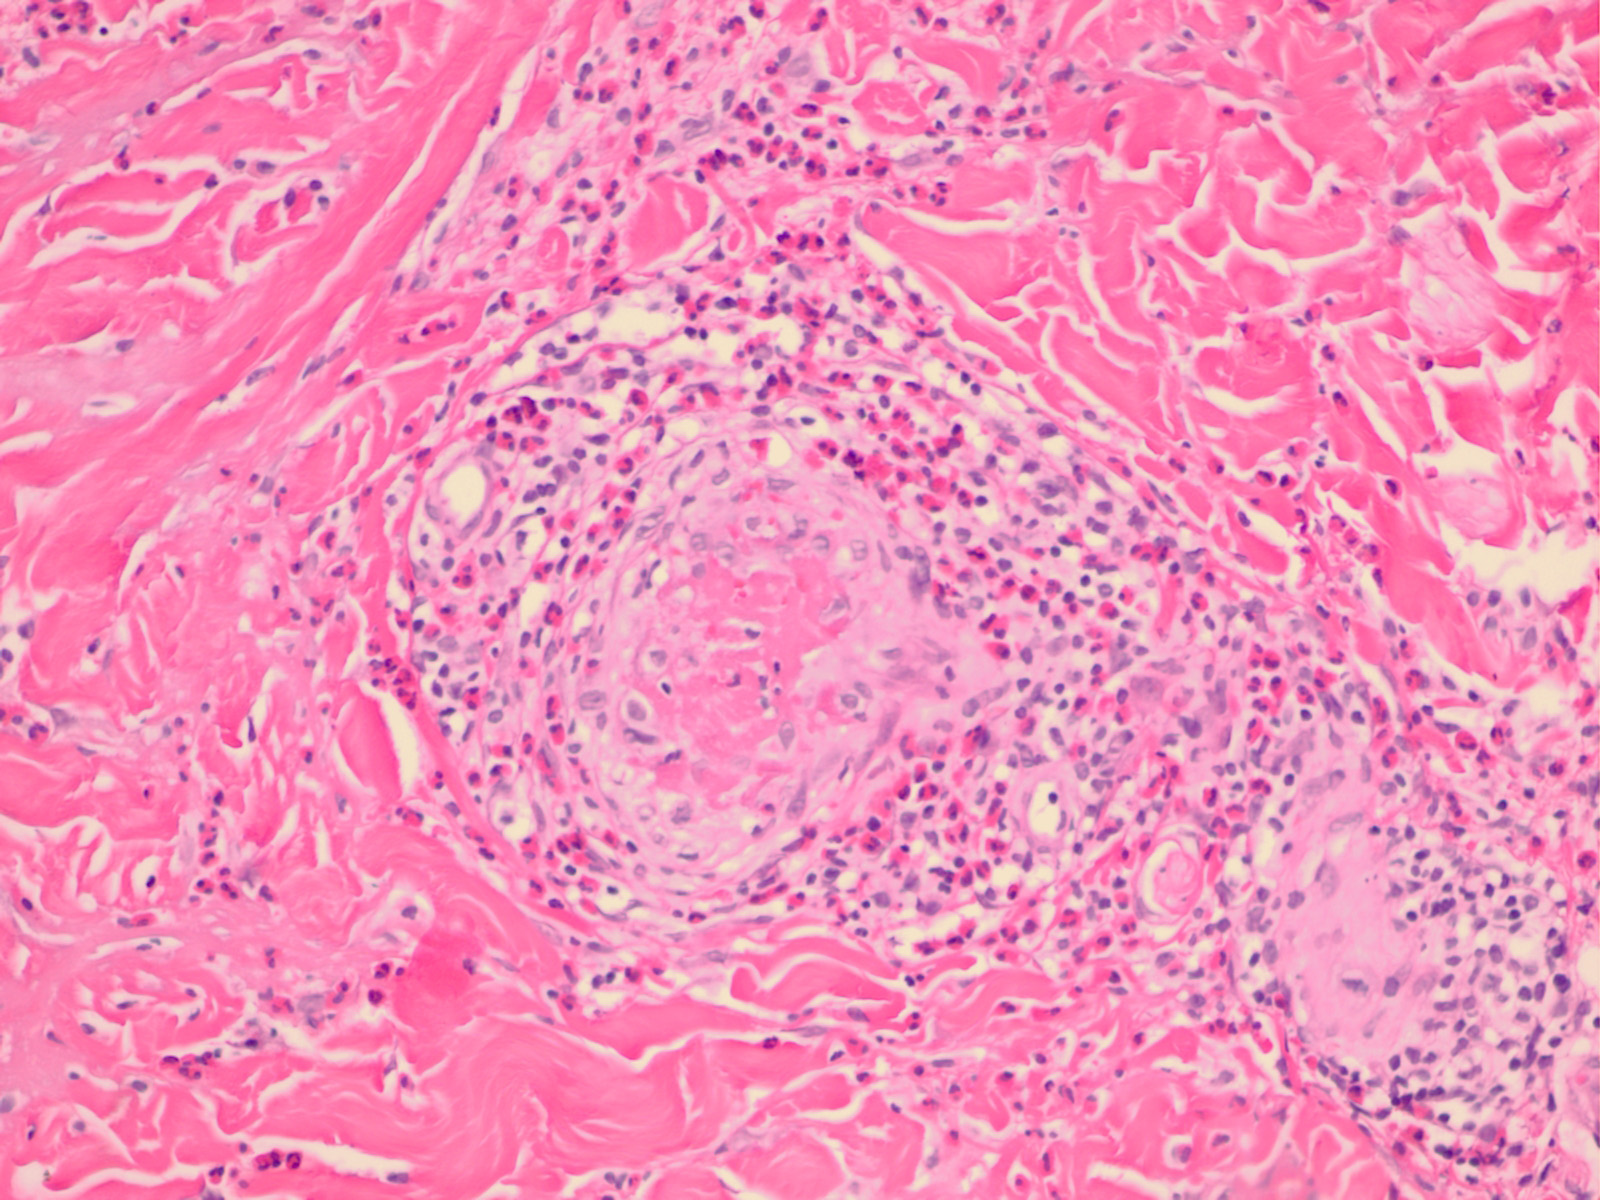

Churg strauss granuloma =حبيبوم شارج شتراوس